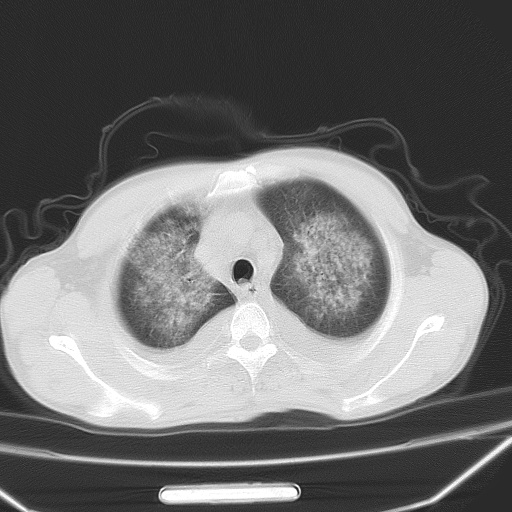

男、42岁、咯血3天。既往有甲亢、贫血、血尿蛋白尿史多年。血象:wbc:6.   中性粒:70.6%。

结合病史考虑双肺泡积血,双侧胸腔少量积液;肺水肿待排(肺水肿症状重)。

双肺堆成磨玻璃影,双测胸腔积液。考虑:肺水肿、间质性肺炎、真菌感染、ards、hiv感染、肺出血。

双肺野对称性磨玻璃影,分布于内中带,双侧胸水,患者有咯血。

1、间质性肺水肿;2、结合临床病史及实验室检查,考虑为肺出血肾炎综合征。    此病需与间质性炎症、粟粒性肺结核鉴别。

肺出血-肾炎综合征又称good-pasture综合征,属少见病,近几年国内有散在报告。此病原因未明,目前多数学者认为与自身免疫有关,即病人体内存在抗-gbm抗体,而病人肺毛细血管基底膜与肾小球基底膜有交叉反应性抗原,从而引起肺泡毛细血管基底膜和肾小球基底膜病变,导致肺出血及肾炎表现。血清抗-gbm抗体阳性,或组织活检见沿肾小球和肺泡基底膜有igg沉积,为本病的3个诊断依据。临床上有许多疾病同时表现为肺出血和肾炎,如系统性红斑狼疮、韦格肉芽肿和增殖性肾小球肾炎等,但这些疾病都不同时具备上述三方面的条件

双肺野广泛对称性磨玻璃影、实变影,以肺门为中心,主要分布于内中带,符合典型肺泡性肺水肿;伴双侧胸腔少量游离积液。结合患者既往病史且咯血就诊,支持多因素(尿毒症等)所致之肺水肿、肺出血、胸水;影像表现暂不考虑心源性水肿,且症状也不太符。需密切随诊结合临床治疗等进一步明确。

心影增大密度略低,双肺磨玻璃样高密度影及双侧胸腔积液,考虑心功能不全继发双肺肺水肿及双侧胸腔积液。心影密度略低,考虑贫血所致。